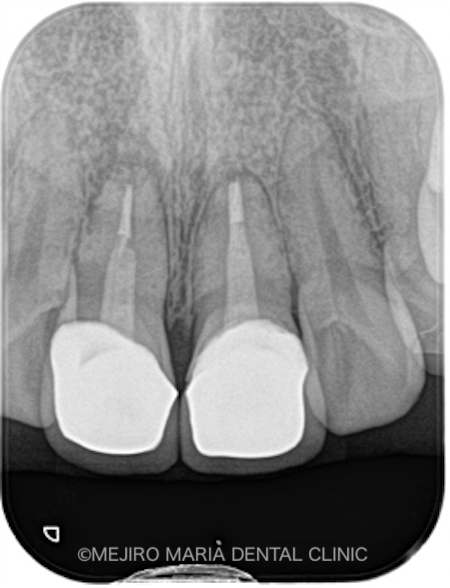

本症例の患者様は、2年前に交通事故で前歯を負傷しました。その際近隣の歯科医院で前歯2本を抜髄し、オールセラミッククラウンを装着されました。しかし、右上の1番はセラミック装着後すぐにろう孔が出現し同時に違和感を覚えるようになったため、治療を行った歯科医院に相談した結果、歯根端切除術を行ったとのことでした。

ところが歯根端切除術を施すも、根尖部の腫脹が改善されなかったため、当院に来院されました(1枚目写真の矢印)。

初診時にCT撮影を行い診査したところ、右上1番の根尖の骨は、根尖性歯周炎により喪失していました。また、左上1番の歯にも小さい病変(根尖性歯周炎)が確認されました(2枚目の写真)。